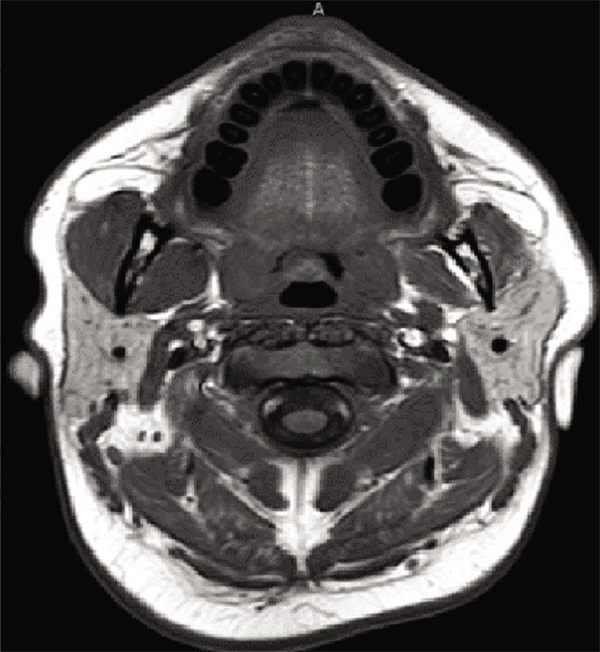

較大三叉神經(jīng)鞘瘤全切,頭頸部神經(jīng)鞘瘤中較常見的神經(jīng)是迷走神經(jīng)和頸部交感神經(jīng)鏈。三叉神經(jīng)鞘瘤是一種不常見的腫瘤,延伸至咽旁間隙少見,文獻(xiàn)中僅報(bào)道過幾次。三叉神經(jīng)...

三叉神經(jīng)鞘瘤表現(xiàn)為錯(cuò)頜畸形,Glasauer和Tandon報(bào)道青少年三叉神經(jīng)鞘瘤的發(fā)病率至少為10%,而Goet以及其他人。圖3:術(shù)前磁共振成像圖描述:對(duì)比T1加權(quán)磁共振成像與52×78×51厘米的軸向、矢...